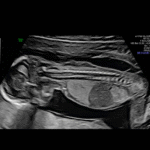

What Happens If the Test Shows High Risk?

If your results indicate a higher risk, our specialists at NESA will guide you through confirmatory diagnostic options like amniocentesis or chorionic villus sampling (CVS) — with expert care and emotional support every step of the way.